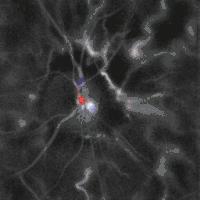

Blood flow in the optic disc revealed by holographic laser Doppler imaging.[4]

Local direction of blood flow with respect to the optical axis revealed by the Doppler spectrum asymmetry in out-of-plane retinal vessels by holographic laser Doppler imaging.[6]

Blood flow in the retina and choroid in the optic disc region can be revealed non invasively by near-infrared laser Doppler imaging.[4] Laser Doppler imaging can enable mapping of the local arterial resistivity index, and the possibility to perform unambiguous identification of retinal arteries and veins on the basis of their systole-diastole variations, and reveal ocular hemodynamics in human eyes.[5] Furthermore, the Doppler spectrum asymmetry reveals the local direction of blood flow with respect to the optical axis. This directional information is overlaid on standard grayscale blood flow images to depict flow in the central artery and vein.[6]